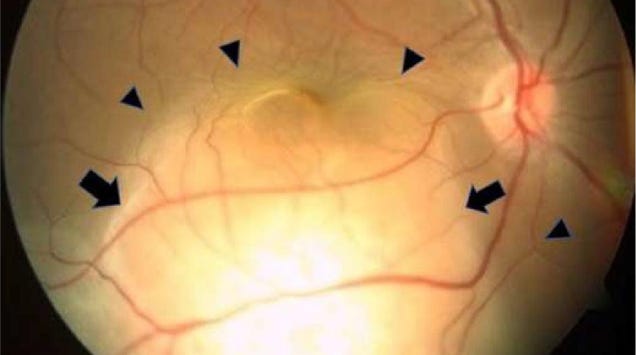

A woman’s blindness in her right eye turned out to have an unexpected and frightening cause: metastatic lung cancer. Doctors in India reported the strange occurrence last month—seemingly the first of its kind ever documented.